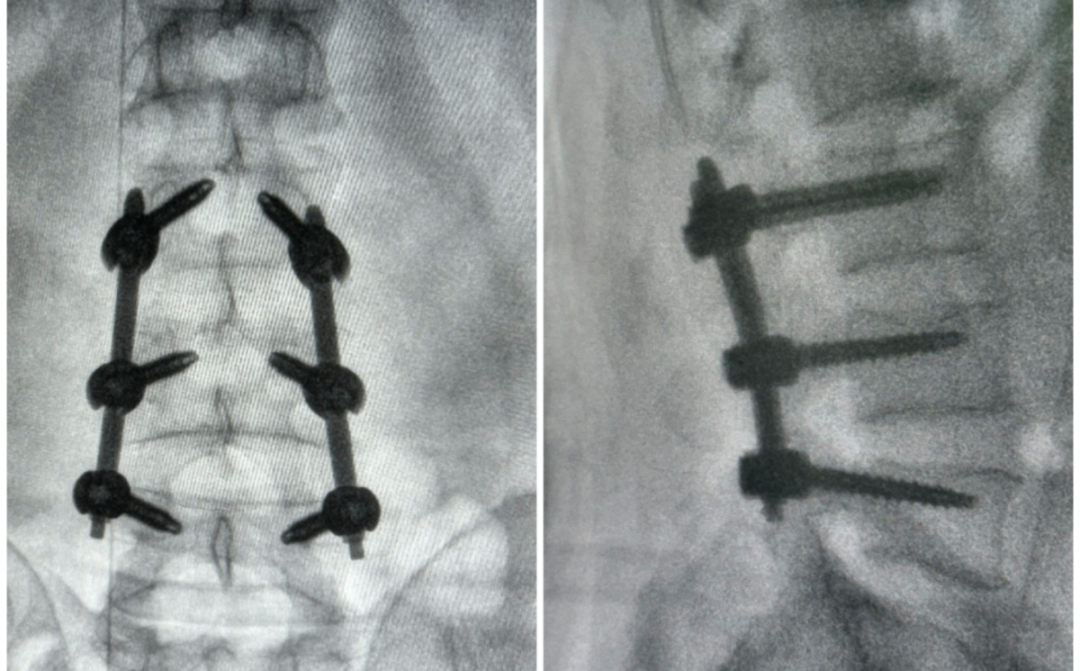

通过采集患者的三维CT数据并将其导入到机器人术前规划系统中,提前确定穿刺位置、角度、深度等信息,制定出适合患者本人的个性化手术方案;通过直观图像定位方法对胸腰椎正侧位进行识别,将正侧位透视图与术前规划数据的结合,即可全方位了解病灶位置及最佳置钉路径,之后机械臂根据软件参数进行“亚毫米级”精准定位,为主刀医生提供精准的手术路径;根据术前规划的螺钉植入路径,在患者背部病变节段两侧做6个小切口(约 2-3cm),最终建立 “工作通道”,术中验证定位准确,汪洋主任完成6枚椎弓根螺钉的植入,证明了手术机器人极高的精度以及稳定性。

经验丰富、磨合多年的骨科手术团队与骨科机器人,二者的结合,不是简单的1+1,而是精准医疗时代“科技+经验”的深度协同,为手术质量与患者安全上了双保险。